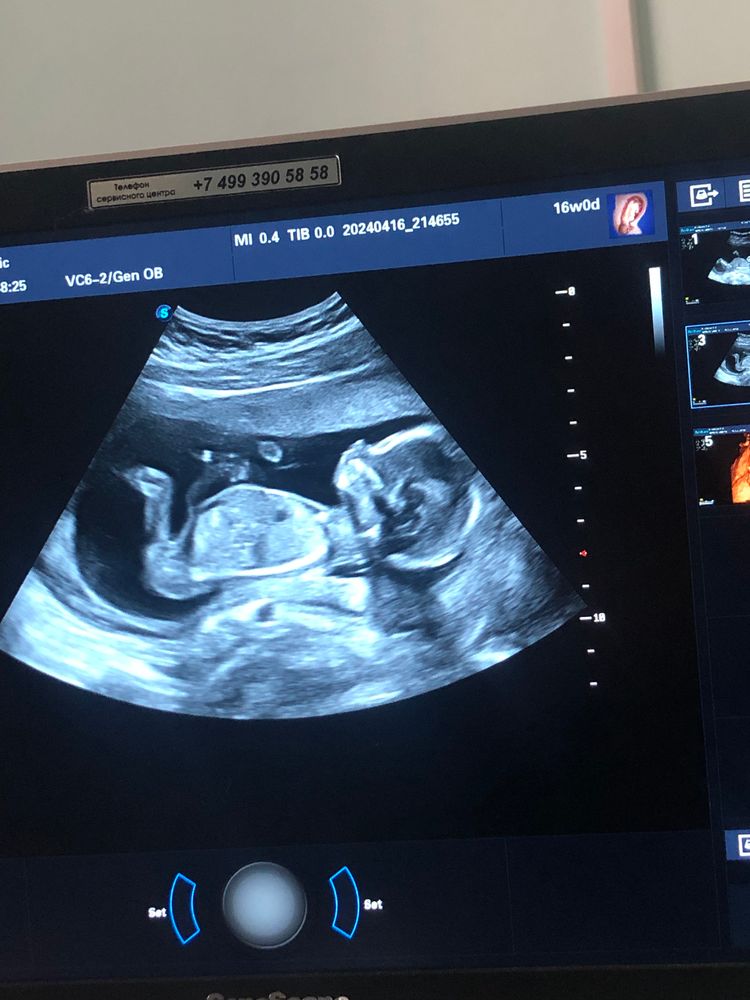

Жду девочку 🩷

Курносенькая такая😍

Таня, даааа, не ясно в кого она такая курносая)))) у нас с мужем вообще другие носы)